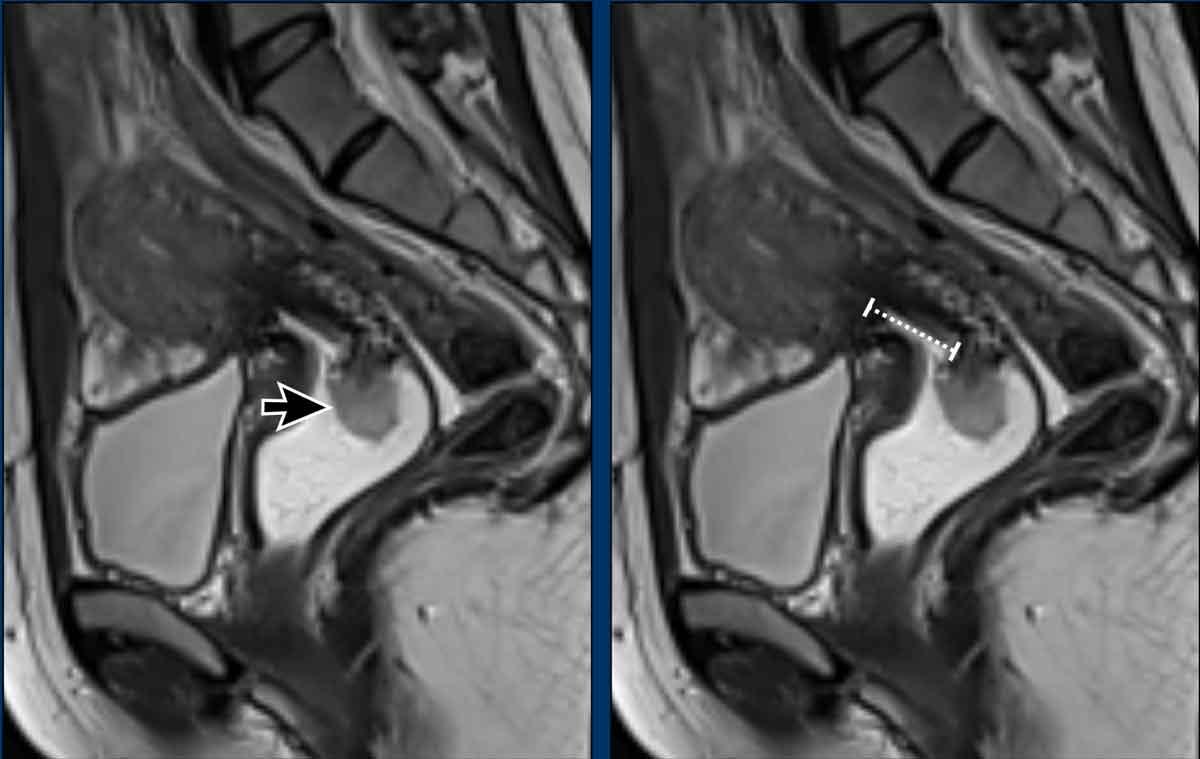

Ví dụ này cho thấy một khối u lớn làm giãn rộng cổ tử cung.

Lưu ý rằng không có xâm lấn thực sự vào vùng cạnh cổ tử cung vì vòng mô đệm giảm tín hiệu của cổ tử cung hoàn toàn còn nguyên vẹn như được chỉ ra bởi các đầu mũi tên.